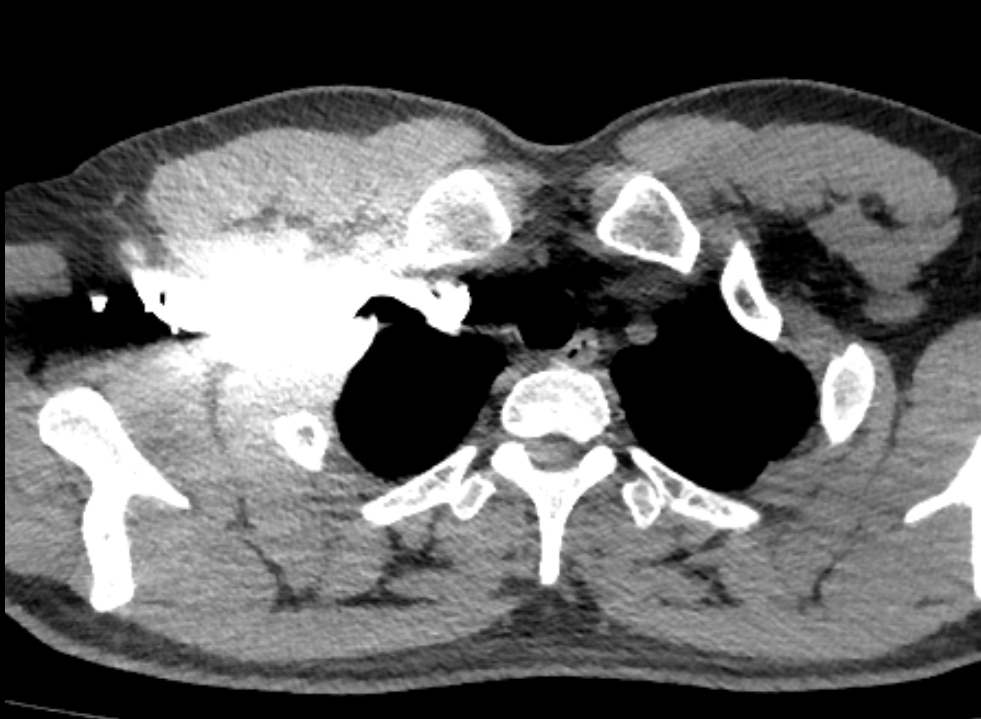

颈总动脉压迫左头臂静脉

左侧锁骨下静脉受主动脉弓挤压,导致对比剂冲入浅表静脉网中

左侧锁骨下静脉受主动脉弓挤压 血管充盈不佳

1)由于受主动脉压迫导致对比剂冲入浅表静脉网中。受阻严重导致团注效果不佳。